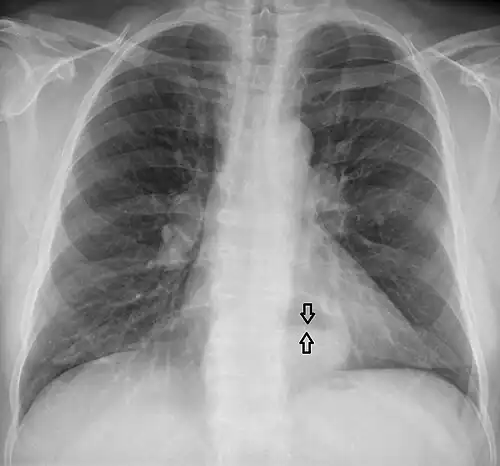

-

This hiatal hernia is mainly identified by an air-fluid level (labeled with arrows). -